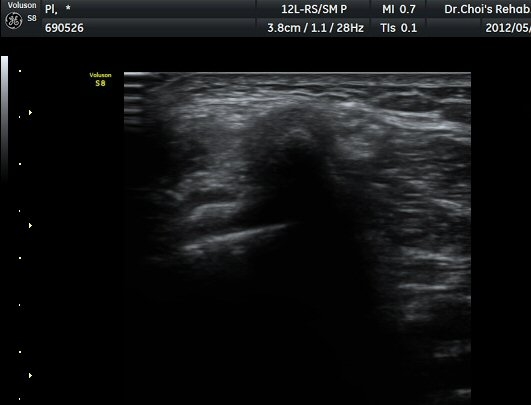

À­´Ù¸®(thigh) ¾Æ·¡ ºÎÀ§ ¿ÜÃø Ⱦ´Ü¸é°Ë»ç¿¡¼­ À̵ιڱ٠³»Ãø¿¡¼­ ÃѺñ°ñ½Å°æÀÌ Á¤»óÀûÀ¸·Î °üÂûµÈ´Ù(±×¸² 1, 2).